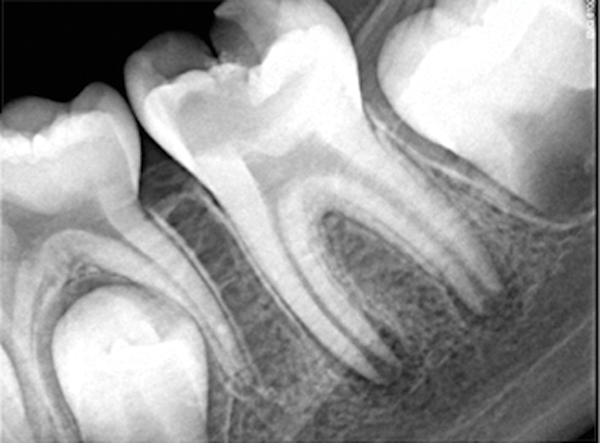

Fig 11. Preoperative radiograph. Courtesy of Dr. Guillaume Jouanny.

Figure 11

Fig 12. Postoperative radiography after full pulpotomy was performed. Courtesy of Dr. Guillaume Jouanny.

Figure 12